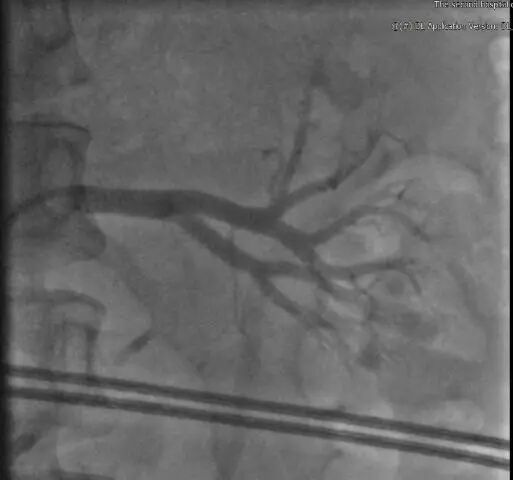

3.基于肾动脉解剖结构的器械选择

解剖特点及器械选择:患者左右肾动脉分支相对迂曲,为了达到更好的降压原则,本着“应消尽消”的原则,选择通过性较好的4F Symplicity Spyral™多级肾动脉射频消融导管,以及6F Launcher RDC导管(55cm).

4.手术策略:左侧消融主干+分支+副肾动脉;右侧消融:主干+分支)

左侧肾动脉及副肾动脉消融

右侧肾动脉及副肾动脉消融

左肾动脉交感神经消融:

主干+分支+副肾动脉

消融点数:35

右肾动脉交感神经消融:

5.RDN治疗总结

左侧肾动脉术后造影

右侧肾动脉术后造影

治疗过程:

左肾有效消融: 35点

右肾有效消融: 35点

副肾动脉有效消融:19点

手术时长: 75 min

造影剂用量: 150 ml

*手术时长:消融导管首次进入至撤出时间